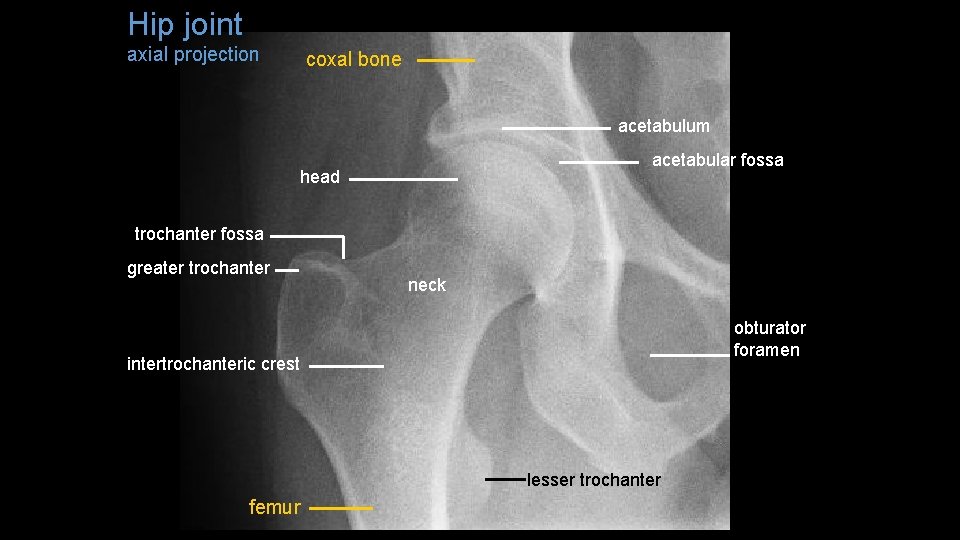

Hip joint axial projection coxal bone acetabulum acetabular fossa head trochanter fossa greater trochanter neck obturator foramen intertrochanteric crest lesser trochanter femur